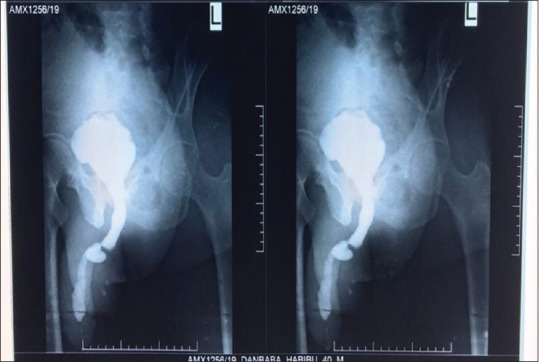

Results: A total of 206 urethroplasties for anterior urethral strictures were evaluated with recurrence of strictures noted in 29 patients and a recurrence rate of 14.1%. Recurrence was higher in long-segment strictures, penobulbar strictures, and postinflammatory strictures. Pedicle flaps were used in 45% of the strictures that reoccurred. Using Chi-square, the length, site, of urethroplasties were statistically significant determinants of recurrence; however, only the site of stricture was found to be statistically significant following logistic regression analysis. The site of recurrence was in the bulbar urethra in 79% and the penile urethra in 21%. The choice of treatment of the recurrent strictures was anastomotic urethroplasty in 76.5%. The mean time to failure in this study was 13 months with a range of 6-120 months.

Conclusion: In this study, the site of stricture was found to be the most determinant of stricture recurrence, with penobulbar strictures mostly implicated. Long-segment strictures were also noted to contribute to some extent in recurrence. These recurrent strictures were mostly short-segment strictures in the bulbar urethra which were amenable to excision and anastomosis to achieve cure.